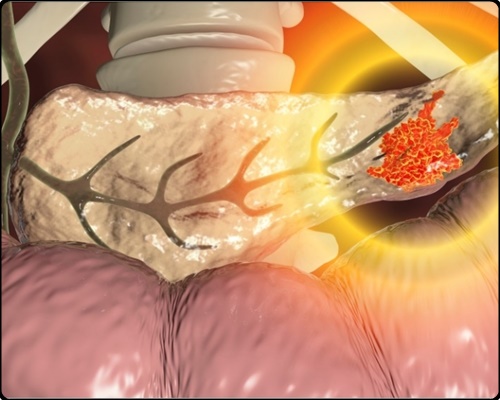

췌장은 소화효소와 인슐린, 글루카곤 등의 호르몬을 분비 및 담당하는 역할을 주로 담당합니다. 그런데 췌장에 종양이 발생하면 췌장암이라고 해요. 췌장암의 경우 사망 확률이 높은 암이라서 조기발견이 무척 중요하더라고요. 다른 질병과 증상이 비슷하며 발견될 때에는 이미 전이가 상당히 진행되는 만큼 조기발견이 힘든 암이기도 해요. 췌장암 초기증상 및 췌장암 등통증 부위에 대해 알아볼게요.

위장에 특이한 이상이 없지만 소화가 계속 잘 되지 않는 증상이 지속된다면 췌장암 초기 증상으로 의심이 가능해요. 췌장을 통하여 암세포가 성장하고, 십이지장으로의 소화액의 통로를 막아 버리기 때문에 출현하는 증상입니다. 췌장의 암세포가 위장에 퍼지면, 식사 후의 통증이나 메스꺼움을 수시로 느끼게 됩니다.

췌장암 초기 증상을 황달에서도 검토할 수 있어요. 황달의 경우 예사로 눈의 흰자위가 노랗게 변하는 증상이고요. 이러한 증상은 췌장 종양이 적혈구를 파괴를 하면 간은 활동을 하는데요. 이를 이용해서 만들어진 빌리루빈이 총담관에 모여 나타난다고 해요.

총담관이란 간을 이용해서 나오는 총 간관과 담낭을 이용해서 나오는 담낭관이 결합되어 만들어진 담낭즙의 이동통로라고 지칭하는데, 이 총담관은 췌장 머리 주위거리에 위치하기에 췌장 머리를 사용해서 췌장 전체까지 퍼진 암이 총담관에 압력을 가하여서 증상이 일어난다고 하고요.